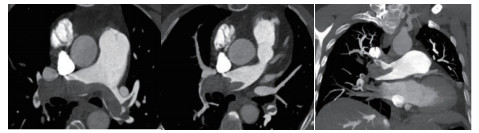

例4 62岁,女性,主诉“活动后气短20 d,加重1 d伴晕厥1次”。患者入院20 d前上近20级台阶后感气促,休息后缓解,未重视。入院前1 d,突发晕厥伴有轻微活动后明显的呼吸困难。既往:左下肢静脉曲张病史3~4年;入院40 d前患者左足跖骨骨折,接受外固定,尚未影响日常活动,未接受抗凝治疗;发现血小板减少数年(血小板维持5.5~8.6 g/L,末次于一年前血小板85 G/L),未明确原因及治疗;血气分析提示pH 7.447,PaCO2 32.2 mmHg,PaO2 85.3 mmHg,SaO2 96.8%;D-Dimer 1 947 ng/mL;FDP 22.84 μg/mL,FBG 2.05 g/L;PLT 51G/L;cTnI 0.52 ng/mL,BNP 299 pg/mL;ALT 318 U/L,AST 300 U/L,CREA 74.8 μmol/L,血Na+、K+、Cl-:正常范围;UCG提示:右心大,肺动脉主干轻度增宽(28 mm),三尖瓣反流(重度),反流面积13.7 cm2,TI法估计SPAP为30 mmHg、左室舒末内径35 mm、左室舒张功能受限(E/A 1:1.5)、未见节段性室壁运动障碍;双下肢静脉超声提示左侧腘静脉不完全血栓。心电图(图 12所示)提示窦性心动过速、SⅠQⅢTⅢ;CTPA显示肺动脉分叉处及双肺亚段充盈缺损(图 13所示)。

| 图 13 入院时CTPA结果显示肺动脉分叉处及双肺亚段充盈缺损 |

入院查体:神志清楚,体温36.5℃,血压120/70 mmHg,脉率110次/min,呼吸22~26次/min,指氧饱和度93%(安静,空气氧),未见乏氧征。双肺呼吸音清,未闻及干湿性啰音,心率110次/min,律齐,P2 > A2,心界无扩大,无杂音,腹软,无压痛,肠鸣音正常。神经系统未见异常。左下肢膝关节以下可见静脉曲张,双下肢无浮肿。入院诊断:急性肺血栓栓塞症(中高危);左下肢静脉曲张并血栓形成;血小板减少症;肝功能不全。处理方法及原因:患者中年,日常生活质量高;入院20 d前虽有症状,但入院1 d前明显加重并出现晕厥发作;两次D-Dimer检查均<2 000 ng/mL,与CTPA显示的血栓负荷不匹配。入院后连续两次检测血小板均低于正常(51~77 g/L)。因考虑病史较长但近期有加重、血小板低等原因系统溶栓治疗出血风险较大,所以给予导管介入碎栓并行肺动脉内溶栓治疗(r-tPA 20 mg)。溶栓2 h后患者症状明显缓解,复查D-Dimer 12 560 ng/mL,序贯肝素抗凝并复查CTPA提示原有血栓明显消失(图 14所示)。

| 图 14 介入溶栓后患者CTPA结果提示明显改善 |